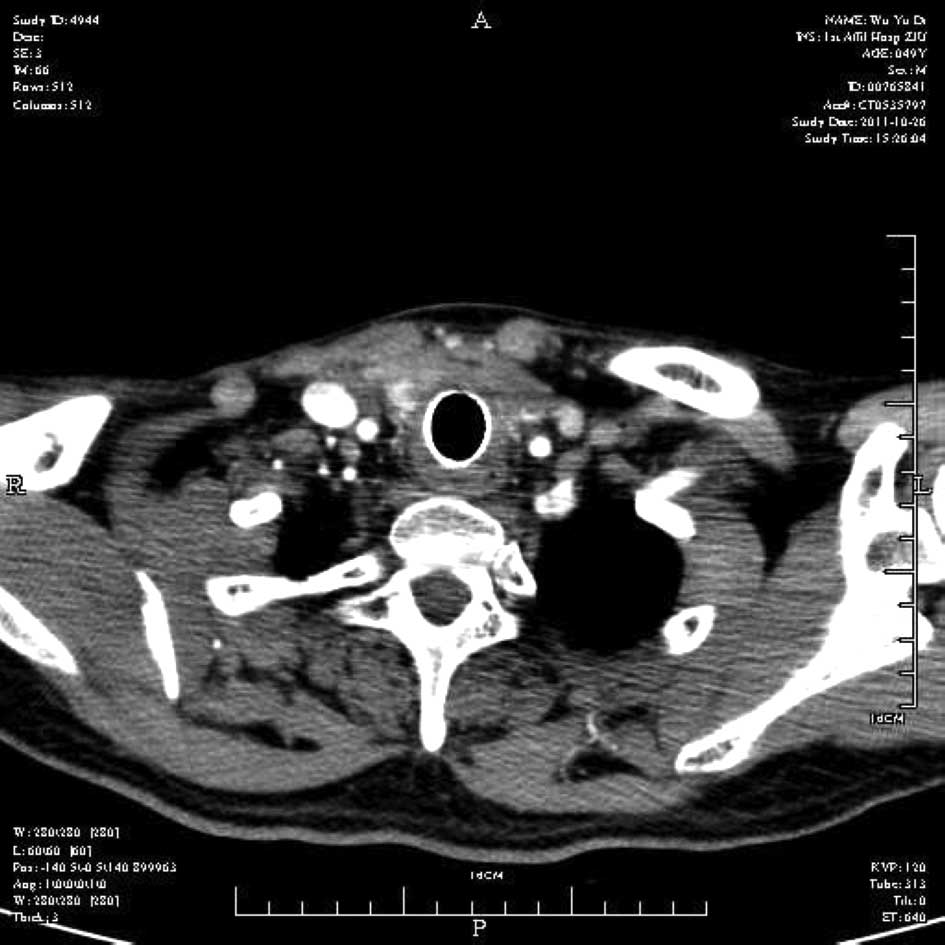

Emergency management of a patient with severe airway obstruction resulting from poorly differentiated thyroid carcinoma: A case report

We present a case of a life-threatening almost complete airway obstruction resulting from poorly differentiated thyroid carcinoma in a 48-year-old male. Airway obstruction may lead to unexpected mortality by suffocation and patients with poorly differentiated thyroid carcinoma usually have a fast deterioration and fatal outcome. In the case presented, we describe a safe and effective treatment strategy. Assisted by femoro-femoral cardiopulmonary bypass oxygenation, a tracheal stent was implanted successfully. Following surgery there were no complications, and chemoradiotherapy resulted in the relief of obstructing symptoms and improved the quality of life of the patient. This case indicates that femoro‑femoral cardiopulmonary bypass provides adequate oxygen support to undergo further management and that tracheal stent implant is an effective emergent measure to relieve severe airway obstruction in patients with poorly differentiated thyroid carcinoma.